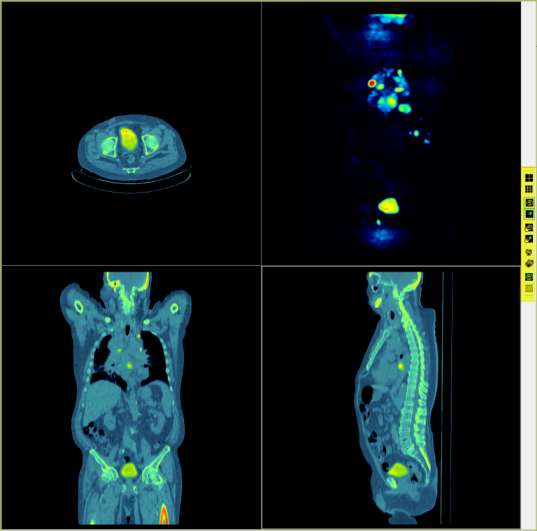

A képfúziós eszköz olyan beépülő modul, amely a PET/CT és SPECT/CT strukturális és funkcionális képeinek szuperponálására szolgál egyetlen kötetben. Az eszközök ortogonális és kötet orientált nézeti vezérlőket, alfa keverést, színspektrum alkalmazást és MIP nézetet tartalmaznak. A beépülő olyan vizsgálatokhoz alkalmazható, amelyek legnagyobb, folytonos képszegmense kiegészítő térbeli felbontási tulajdonságaiban megegyezik, ami azt jelenti, hogy egyetlen gép készítette őket egyetlen folyamat részeként.

A fúziós beépülő egy nézegető területből és egy eszköztárból (kiemelt terület) áll.

Kijelző elrendezés

A két elsődleges elrendezés más nézetben mutatja a képeket:

| Elrendezés | Leírás |

| 4-képes | Kijelzi az egyéni vagy a fúziós képsorozatot mindhárom ortogonális, plusz egy MIP nézetben. |

| 9-képes | Három sorban mutatja a képsorozatot mindhárom ortogonális nézetben. Az első három sor a szerkezeti képet mutatja. A második három sor a működési képet mutatja. Az utolsó sor a fúziós képet mutatja. |

MIP képnézet

A MIP nézet egyetlen vagy egy fúziós képet jelenít meg 4-képes megjelenítési módban.